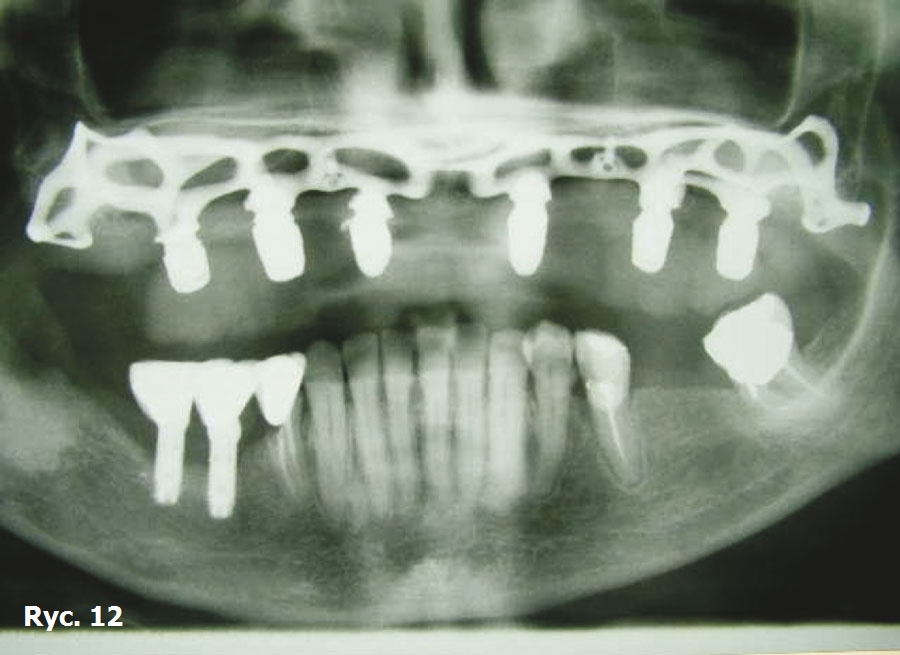

Wyniki badania TK oraz model stereolitograficzny pozwoliły na wykonanie dwóch oddzielnych siatek wszczepu podokostnowego w obrębie łuku górnego (ryc. 9), które zostały później wszczepione (ryc. 10) oraz połączone ze sobą, aby wspólnie przenosić siły żucia (ryc. 11), stanowiąc podparcie dla estetycznego uzupełnienia protetycznego stałego (ryc. 12, 13). Zabieg chirurgiczny przebiegł bez powikłań. Przysłana z Karaibów kartka pocztowa z trzema słowami „drugi miesiąc miodowy” potwierdziła, że cała wykonana przez lekarza praca zakończyła się sukcesem.

Wszczepy podokostnowe - przypadek 2 (ryciny)